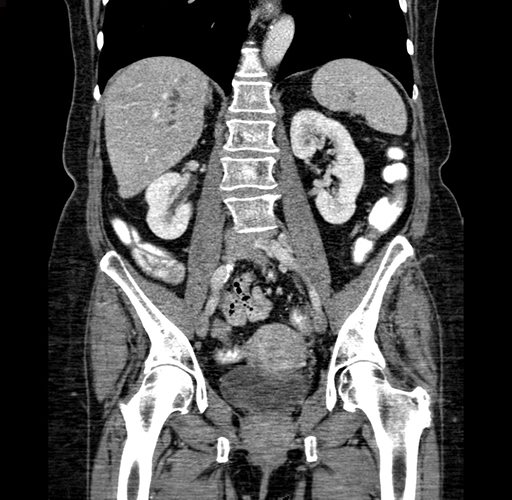

Pre-Chemo: Coronal Venous